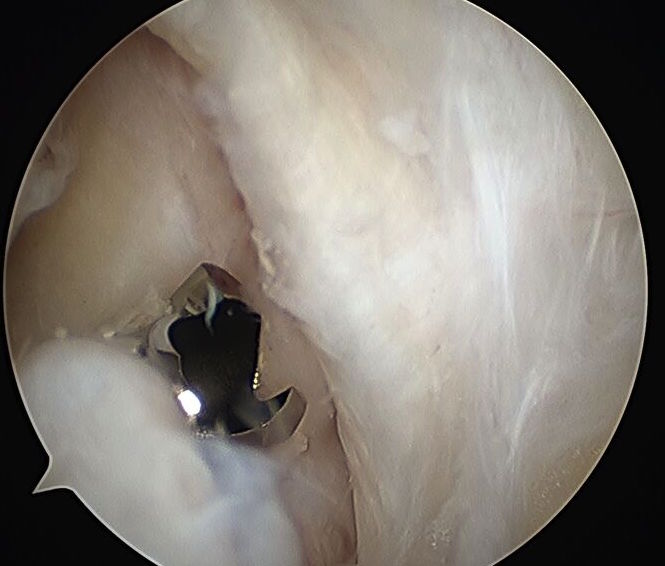

- pass sutures through meniscal root (either labral suture passer or rotator cuff suture passer)

- retrieve through tunnel with houston suture passer

- tie over endobutton